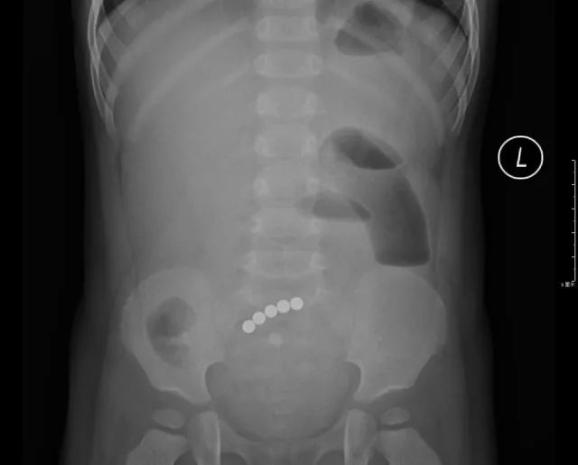

2018年11月,13岁的浩浩(化名)被爸妈带到深圳市儿童医院泌尿外科门诊。一周前,浩浩的下腹部开始隐隐作痛。尤其是跑步时,腹部沉沉的,痛得也更厉害。熬了几天后,就连小便也会痛。

医生耐心询问下才知道,原来浩浩向自己的“小鸡鸡”里塞过“巴克球”!而且塞了10多个,已经一年半以前的事了。

拍完X光片后,医生发现:浩浩下腹部左侧像是挂了一道环形“手串”,10多颗珠子紧紧连在一起,固定在膀胱左侧壁。尿检后发现,浩浩已经有了慢性膀胱炎,细菌正在尿液中滋长。